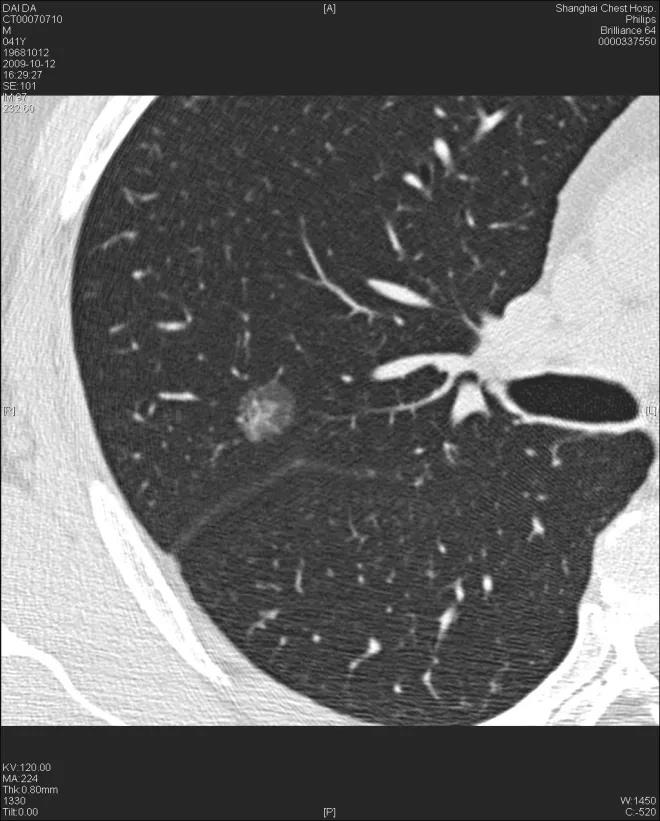

右上肺直径约6 mm左右纯磨玻璃结节(pGGN),平均CT-609 HU。手术病理AAH。